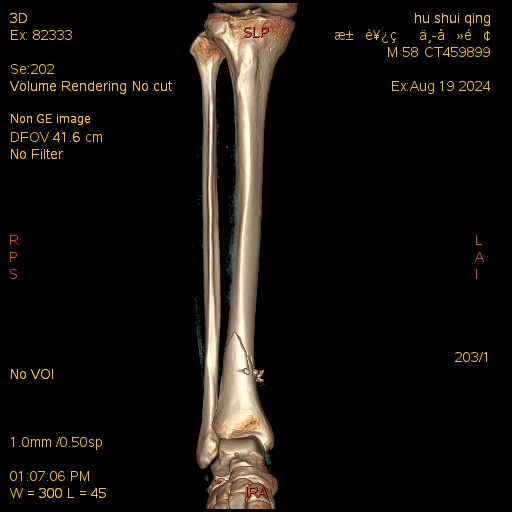

术前三维CT

患者胡某,男,58岁,因锐器切割致右下肢开放性损伤3小时入院。入院后诊断为:1.开放性胫骨下端骨折2.下肢神经的损伤3.下肢血管的损伤4.跟腱断裂5.下肢肌腱损伤。患者入院后立即急诊行右下肢清创术+胫神经缝合术+胫动脉缝合术+跟腱缝合术+胫骨远端克氏针临时固定术。术后3周后患者开放伤口处皮肤顺利愈合并拆线,拟进行二次手术对胫骨远端骨折进行终极固定。骨伤医院院长梁卫东及创伤骨科杨阳主任医师团队对该患者开展详细的病情讨论,并制定详细周密的手术计划及术后康复计划,同时在患者及其家属知情同意后,实施胫骨远端骨折逆行胫骨髓内钉内固定术,并取得成功。